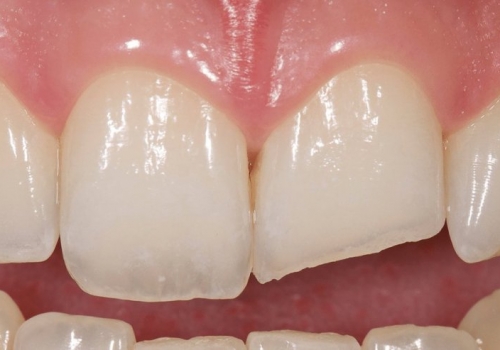

Bu tip zədələnmələrin bu sahədə təcrübəsi olan yüksək ixtisaslı həkim tərəfindən həyata keçirilməsi olduqca önəmlidir. Əks təqdirdə yalnış müalicə dişlərin erkən itirilməsinə səbəb ola bilir. Doğru yanaşma ilə isə ciddi zədələnmələrdən sonra belə zədələnmiş dişləri bəzən müəyyən bir müddətə bəzən isə həmişəlik bərpa etmək mümkün olur.